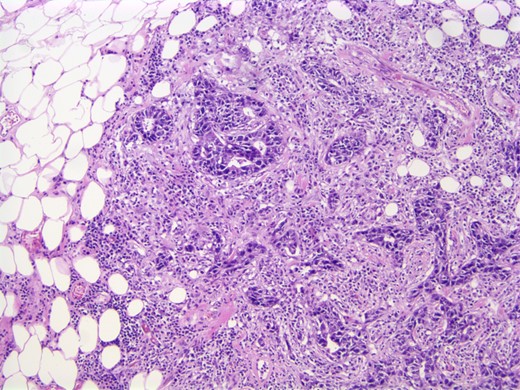

A computed tomographic (CT) scan of her chest with contrast revealed moderate right axillary lymphadenopathy and a lesion in the upper outer quadrant of the right breast measuring 1.3 × 1.2 cm (Fig. 1). A positron emission tomography (PET) scan showed a small intense focus on the right lateral breast consistent with carcinoma, significant right axillary lymphadenopathy and intense fluorodeoxyglucose hypermetabolic activity consistent with metastatic spread. Additionally, enlarged lymph nodes extending along the upper chest wall just inferior to the subclavian vessels and posterior to the pectoralis muscles were seen. A needle biopsy of the mass revealed an extensive involvement of poorly differentiated infiltrating carcinoma (Fig. 2). The tumor showed large nuclei with eosinophilic cytoplasm and prominent nucleoli consistent with apocrine differentiation (Fig. 3). There was a significant inflammatory response to the infiltrating tumor noted. No lymphovascular invasion was identified within the core biopsies. The specimen was estrogen and PR negative as well as HER-2/neu negative.

Photomicrograph: apocrine differentiation and inflammatory response.